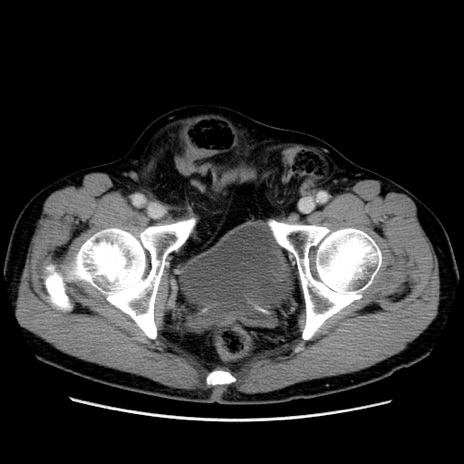

症例34(横断像)

【症例】60歳代 男性

【主訴】右鼠径部膨隆

【現病歴】1年程前より右鼠径部膨隆あり。自己にて還納可能だったため放置していた。3時間前より右鼠径部の脱出を認め、還納困難となり受診。

【既往歴】高血圧

【身体所見】右鼠径部に小児頭大の膨隆あり。弾性硬であり、用手還納は困難。左鼠径部にも膨隆を認める。脱出はなし。

【データ】WBC 15500、CRP 測定なし